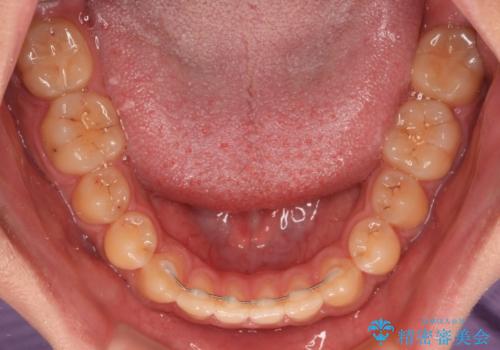

装置除去後もトレーニングを継続されているようで、後戻りによるスペースは今のところ認められておりません。